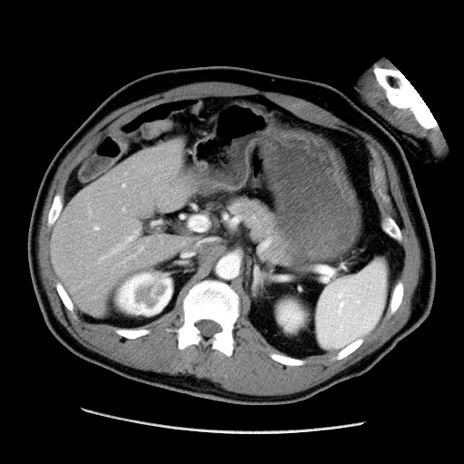

冠状断像

【症例】50歳代男性

【主訴】腹痛

【現病歴】AVMからの被殻出血のため回復期リハ病棟入院中。 本日午後3時頃急に下腹部痛が出現した。

【既往歴】AVM、被殻出血、虫垂炎、高血圧

【身体所見】意識晴明、左半身不全麻痺、会話の理解は良好、36.5°C、腹部:膨隆、全体に板状硬、下腹部正中に圧痛点あり、反跳痛-、筋性防御不明、右下腹部にope scar

【データ】WBC 9400、CRP 0.06